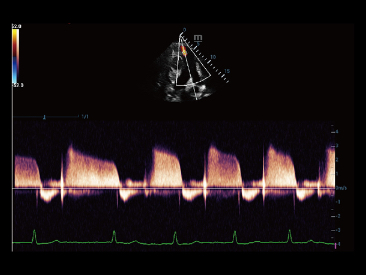

Oprócz uzyskiwania jako?ci obrazu typowego dla aparatów klasy premium, Resona 7 rozszerza mo?liwo?ci klinicznych badań USG dzi?ki rewolucyjnej funkcji V Flow, s?u??cej do oceny hemodynamiki naczyń, a tak?e najlepszej na rynku funkcji inteligentnego, automatycznego uzyskiwania p?aszczyzny na podstawie zestawów danych obj?to?ciowych 3D, umo?liwiaj?cej diagnozowanie stanu Centralnego Uk?adu Nerwowego u p?odu. Aparat Resona 7 ??czy w sobie najbardziej intuicyjn?, wielodotykow? obs?ug? za pomoc? gestów oraz wszystkie kluczowe funkcje kliniczne, co sprawia i? jest prawdziwym liderem we wprowadzaniu innowacji w ultrasonografii.